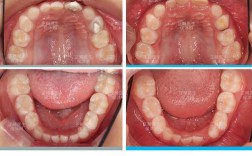

儿童口腔发育可分为乳牙期(3-5岁)、替牙期(6-12岁)和恒牙早期(11-14岁),每个阶段的牙齿和颌骨状态不同,矫正目标和时机也存在差异。

此时儿童大部分恒牙已萌出(除智齿外),颌骨发育接近完成,牙齿移动效率高,是常规固定矫治的黄金时期,主要针对牙列拥挤、牙齿错位、深覆盖(龅牙)、开颌(上下牙无法咬合)等问题,通过固定矫治器(如金属托槽、陶瓷托槽)或隐形矫治器调整牙齿排列,改善咬合功能和面部美观,这一阶段矫正效果稳定,周期相对较短(通常1.5-3年),是多数家长认知中的“正畸年龄”。